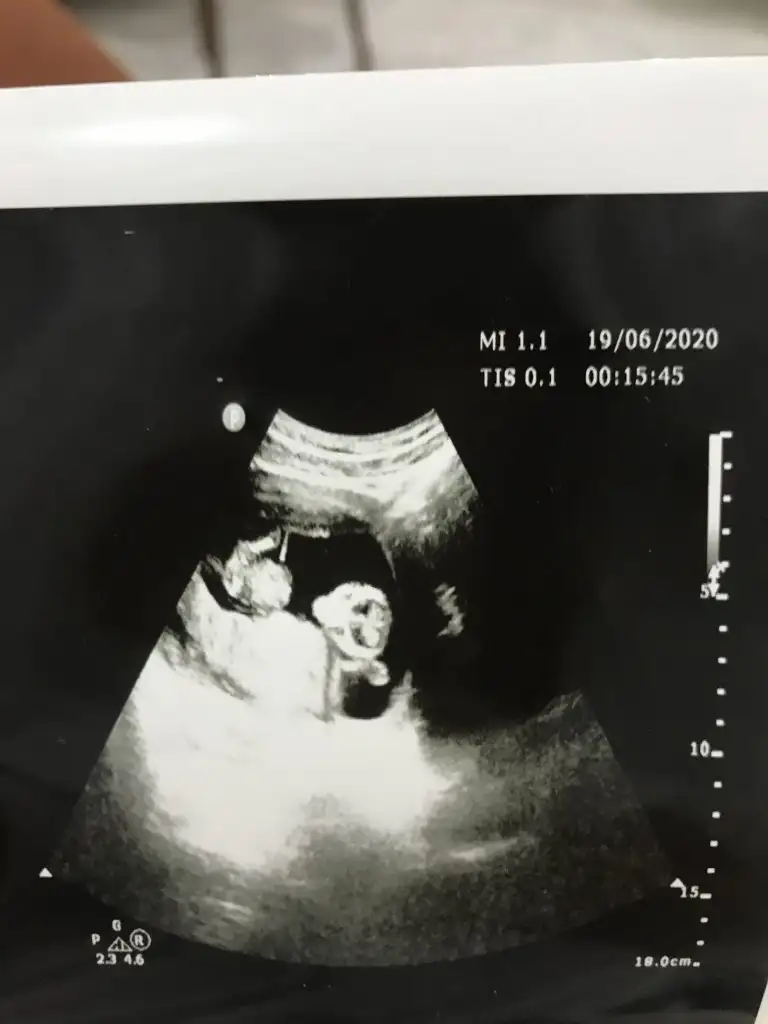

Bunlar net değilBi de bu resimler var.

Kaç haftalık usg sanki erkek gibi eminde olmadım 11 12 13 haft usgler olmalı tekrar usg paylaşınMerhabalar tahmininizi çok merak ediyorum :)

Üçlü taramada büyük ihtimalle kız olduğu söylendiNet degil usg tek tek çekermisiniz usgler yada başka usg olursa paylaşın 12-13 haftalarda olabilir şimdilik eminde değilim kız gibi gibi emin değilim tekrar usg paylaşın